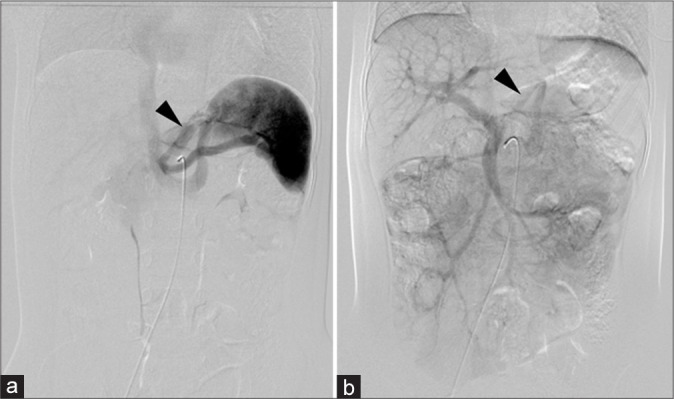

先天性门静脉系统分流(CPSS)是一种罕见的血管异常,其中门静脉血液流入体循环而不经过肝脏。大约每3万到5万例活产婴儿中就有1例。我们报告了一位11岁的肝外CPSS患者,并进行了长期随访。最初的临床表现没有明显的异常。随后的评估显示氨(NH3)和总胆汁酸(TBAs)略有升高。2岁和11岁时两次血管造影证实门静脉和左肾静脉分流,随着患者年龄的增长,血流优势逐渐从腹腔动脉-脾静脉系统转移到肠系膜上动脉-肠系膜上静脉系统。由于并发症的风险,我们进行了经导管分流栓塞,使用12个线圈实现了完全的分流栓塞。栓塞后,NH3和TBA水平恢复正常,患者无症状。该病例强调了CPSS干预时机的重要性,特别是在血流动力学变化的情况下,并强调了儿科CPSS最佳干预时机的进一步研究的必要性。

Congenital portosystemic shunt (CPSS) is a rare vascular anomaly in which portal vein blood flows into the systemic circulation without passing through the liver. They occur in approximately 1 in 30,000-50,000 live births. We present an 11-year-old patient with an extrahepatic CPSS managed with long-term follow-up. The initial clinical presentation showed no significant abnormalities. Subsequent assessments revealed slightly elevated ammonia (NH3) and total bile acids (TBAs). Two times angiography at the ages of 2 and 11 years confirmed a shunt between the portal vein and left renal vein, with a gradual shift in blood flow dominance from the celiac artery-splenic vein system to the superior mesenteric artery-superior mesenteric vein system as the patient aged. Due to the risk of complications, transcatheter shunt embolization was performed, utilizing 12 coils to achieve complete shunt embolization. Post-embolization, NH3, and TBA levels normalized, and the patient remained asymptomatic. This case highlights the importance of timing in CPSS intervention, particularly with shifting hemodynamics and underscores the need for further studies on optimal intervention timing in pediatric CPSS.